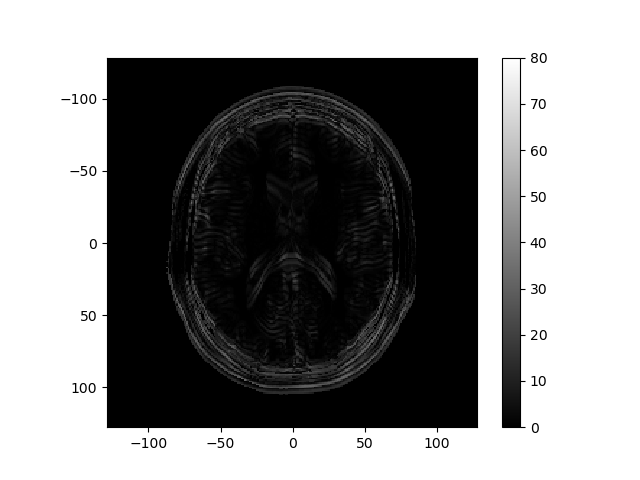

The left image below shows the magnitude of the k-space data obtained for an MRI, and the right image shows the reconstructed image.

Consider how the image would change if the k-space data were multiplied by \sin^2(\cdot) or \cos^2(\cdot) of k_r or k_c. Below are several k-space representations that have been distorted in this way. In each case, assume that only the magnitude of the k-space data is changed. Match each k-space image with the corresponding reconstructed image, and enter your results from the corresponding pull-down list.